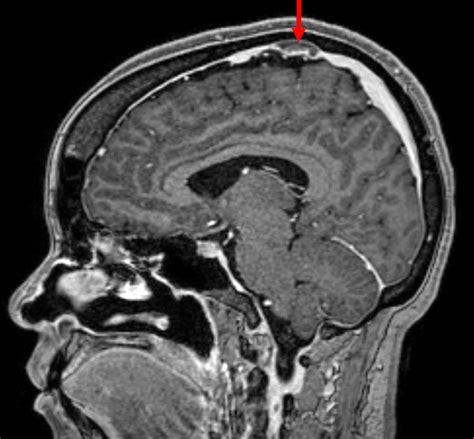

Post-Dural Puncture Headache

Post-dural puncture headache (PDPH) is a specific type of headache that can occur after a spinal tap or epidural. It is caused by a leak of cerebrospinal fluid (CSF) from the puncture site. PDPH typically occurs within a few days after the procedure and can be quite debilitating. Symptoms of PDPH include:

• Throbbing Headache: Often worse when sitting or standing and relieved when lying down.

• Neck Stiffness: Often felt in the back of the neck.

• Nausea and Vomiting: Can be associated with severe headaches.

• Tinnitus: Ringing in the ears.

• Photophobia: Sensitivity to light.